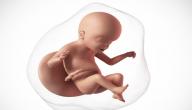

يُعَدُّ الأسبوع الواحد والعشرون بداية الشهر السادس، والذي يتميَّز بتباطؤ مُعدَّل النموِّ، إلّا أنَّ الأعضاء لا زالت تنضج، وبدأت الدُّهون بالتكوُّن لتمنح الجنين الشعور بالدفء، وفي هذه الفترة تبدأ الغُدَد الزيتيّة بإفراز مادَّة شمعيّة تُغطِّي الجلد لتبقيه مرناً داخل السائل الأمينوسيّ، أمّا الأسنان فقد بدأت براعم الأسنان الدائمة بالتكوُّن.[١]

في هذه الفترة من عمر الجنين يُصبح شكله أقرب ما يكون إلى الطفل الرضيع مع اختلاف الحجم، حيث يكون وزنه ما يقارب 453.59 غم، ويبلغ طوله حوالي 27.94 سم، ويُمكن رؤية ذلك عن طريق التصوير بالموجات فوق الصوتيّة، أمّا العيون فقد تكوَّنت أجزاؤها البصريّة جميعها ما عدا القزحيّة، حيث لا تحتوي بعد على أيّة صبغة، وتكون الجفون والحواجب قد تكوَّنت.[٢]